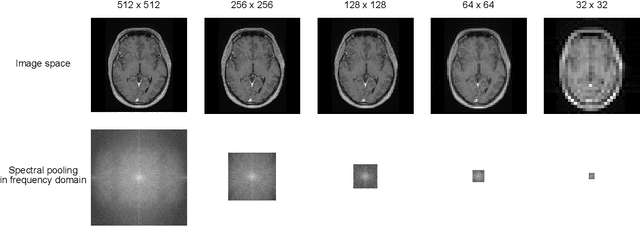

Abstract:Objectives: Present a novel deep learning-based skull stripping algorithm for magnetic resonance imaging (MRI) that works directly in the information rich k-space. Materials and Methods: Using two datasets from different institutions with a total of 36,900 MRI slices, we trained a deep learning-based model to work directly with the complex raw k-space data. Skull stripping performed by HD-BET (Brain Extraction Tool) in the image domain were used as the ground truth. Results: Both datasets were very similar to the ground truth (DICE scores of 92\%-98\% and Hausdorff distances of under 5.5 mm). Results on slices above the eye-region reach DICE scores of up to 99\%, while the accuracy drops in regions around the eyes and below, with partially blurred output. The output of k-strip often smoothed edges at the demarcation to the skull. Binary masks are created with an appropriate threshold. Conclusion: With this proof-of-concept study, we were able to show the feasibility of working in the k-space frequency domain, preserving phase information, with consistent results. Future research should be dedicated to discovering additional ways the k-space can be used for innovative image analysis and further workflows.